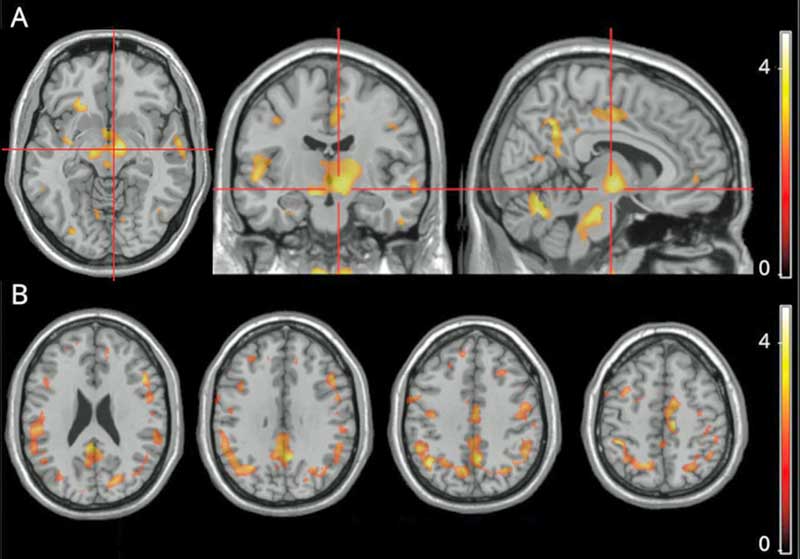

The bright spots reflect correlations between fatigue and microglial activation. The bright spots in the middle are located in the substantia nigra of the basal ganglia

The main finding was a “strong correlation” between the amount of fatigue the MS patients were experiencing and the activation of microglial cells in a part of the brain called the substantia nigra. Secondary analyses found microglial activation in other parts of the brain (right precuneus, parahippocampal gyrus, putamen, thalamus, juxtacortical white matter) were also associated with increased fatigue.

All in all, the authors reported finding evidence of “widespread” microglial activation in the brains of MS patients with high rates of fatigue. Both Younger’s and Nakatomi’s ME/CFS study, and the recent fibromyalgia study, found evidence of “widespread” neuroinflammation as well.

Fatigue is one of the most common and disabling symptoms of MS, yet it is not, oddly enough, related to the lesions which cause the movement and other problems in the disease. Some studies have found brain abnormalities that are associated with fatigue in MS, but it’s never been clear what’s causing them. A small exploratory MS study may have provided an answer – microglial activation and neuroinflammation.

As in ME/CFS and FM, widespread areas of neuroinflammation in the brain were found in MS. It was the key finding of the study, however, that aroused the most interest. The part of the brain most associated with the fatigue in MS was the substantia nigra of the basal ganglia. Damage to the basal ganglia has long been proposed to play a crucial role in the fatigue in ME/CFS and other diseases, and the authors readily cited past findings in ME/CFS.